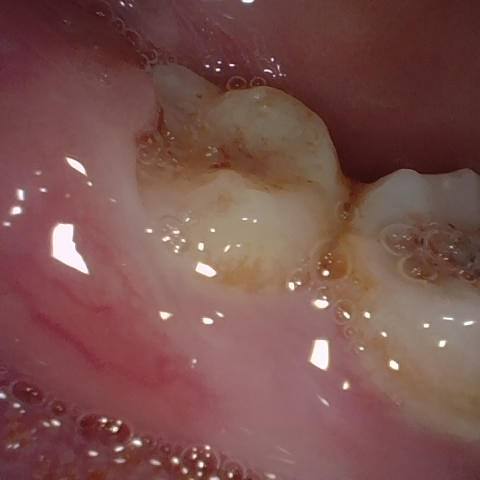

Annotated as "Good"